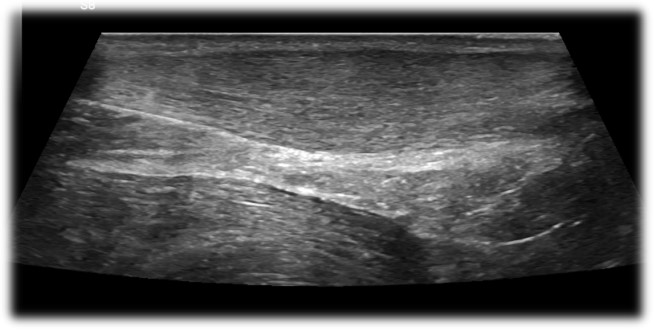

Ultrasound can very clearly show the difference between a normal Achilles tendon (Right top) and one that has tendinopathy (Right Middle) as the tendinopathic tendon is often significantly thicker than a normal Achilles tendon.

In addition to that a tendinopathic tendon tends to be hypoechoic. What that means is that the tendon is less bright on ultrasound. If the tendon has more fluid in it i.e. is more swollen than automatically it appears darker on ultrasound.